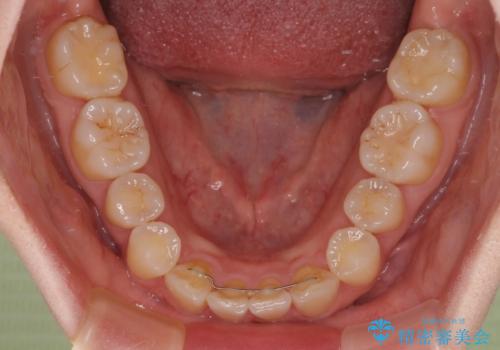

- 上顎前歯の突出感を気にして来院された患者様です。

下顎前歯2本が先天欠損しており、上顎歯列に対して、下顎歯列がアンバランスに小さい状況でした。

左右上顎側切歯2本が矮小歯であるため、上顎の抜歯ではなく、IPR(歯と歯の間を削る)と歯列全体の後方移動によってバランスを整えることとしました。

歯列のバランスが悪く、インビザライン矯正特有の奥歯の噛みにくさがなかなか改善されず、治療期間が長期化してしまいました。